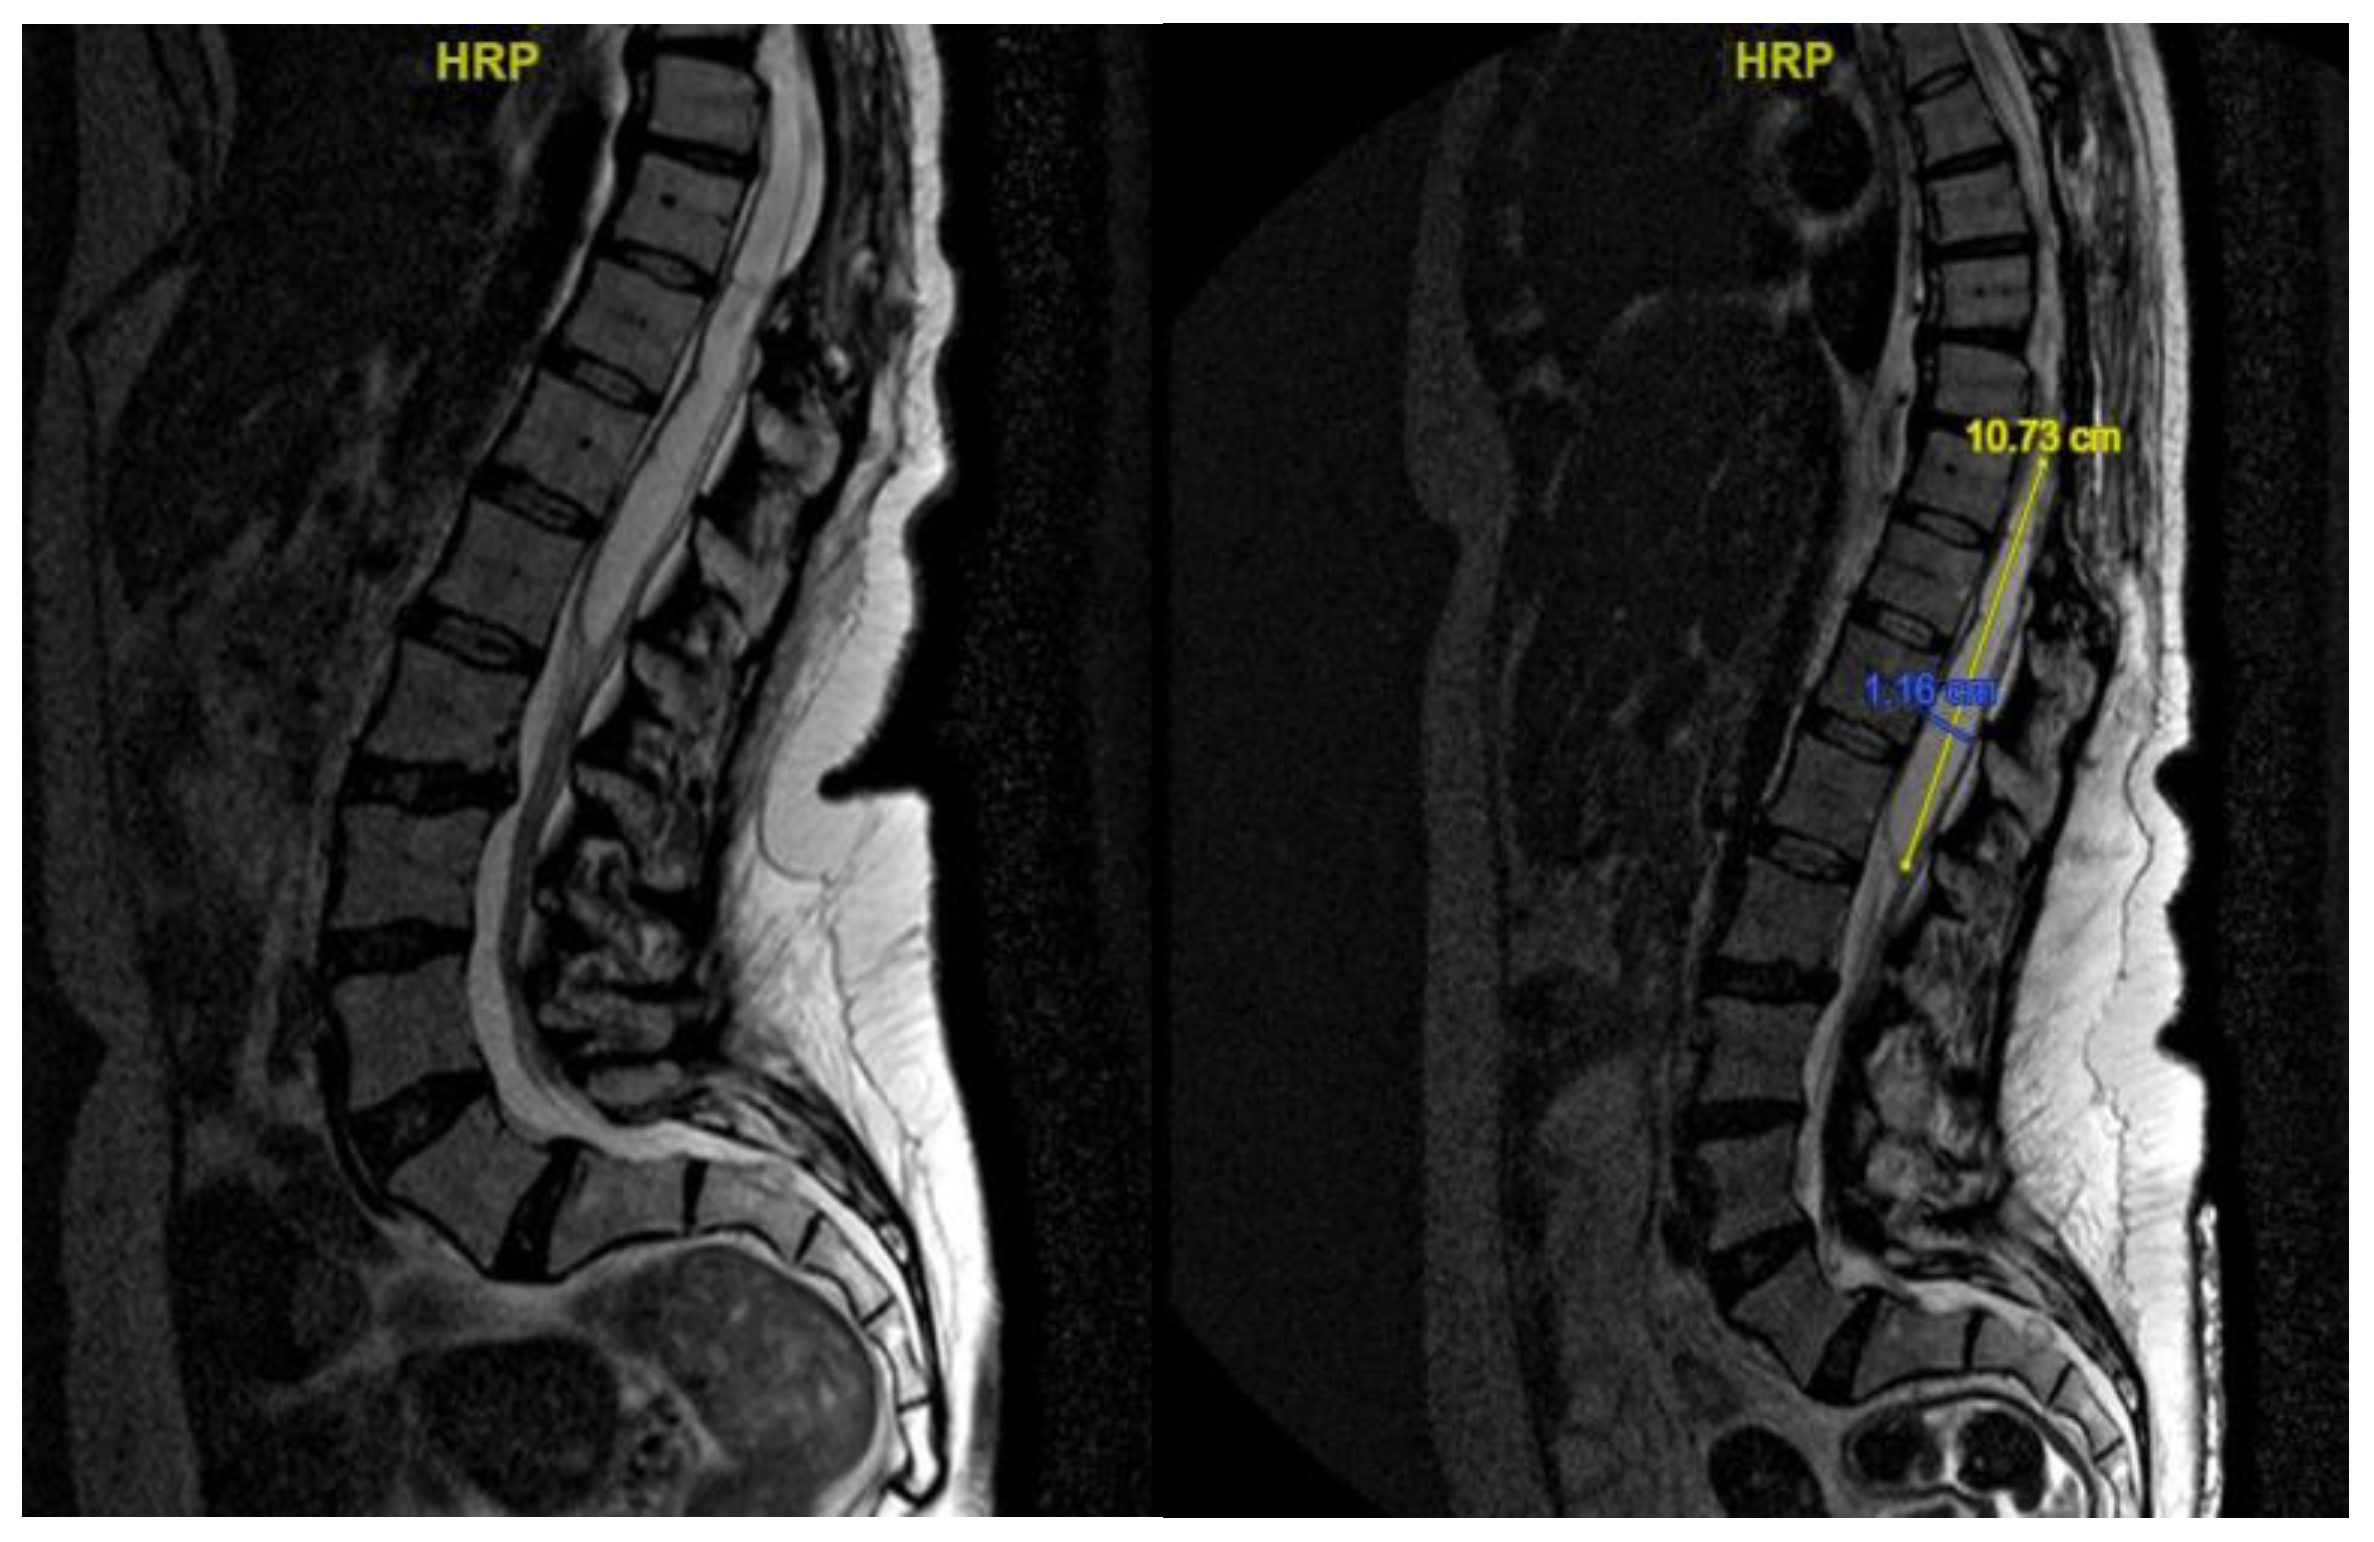

A second surgery addressed the syringomyelia with laminectomy (D7-D10) and adhesion lysis: postoperative MRI showed resolution of the cyst but persistent malacic changes. A cerebrospinal fluid fistula was treated surgically. After further deterioration and expansion of the syringomyelic cavity, a third surgery including reopening of the previous surgical incision and exposure of the laminectomy allowed the dissection of numerous scar septa both above and below the dural plane, freeing the spinal cord circumferentially. A myelotomy was performed to drain the syringomyelic cavity and establish communication with the subdural space, placing of a syringoperitoneal shunt and additional adhesion lysis [Figure 7]. Post-operative MRI indicated reduced syringomyelic size [Figure 8]. The patient remains clinically stable after 4 years of follow-up.

Neurological examination revealed ataxic gait and diffuse proprioceptive hypoesthesia in the lower limbs. MRI of the thoracolumbar spine with contrast identified intradural cystic collections at D8-D11, located dorsal to the spinal cord and causing signs of myelopathy [Figure 9].

The patient underwent decompressive laminectomy using piezosurgery at the affected spinal levels to remove the cysts and release arachnoid adhesions. Intraoperative monitoring of sensory and motor evoked potentials was performed. After exposing the dural plane, a full laminectomy was carried out, revealing the cystic lesion enveloping the spinal cord and numerous septa anchoring to neural structures, obstructing normal cerebrospinal fluid flow. The cyst was fenestrated into the subarachnoid space, and the adherent perimedullary structures were dissected to restore cerebrospinal fluid circulation and initial pulsatility of the exposed neural structures. Post-operatively, the patient exhibited lower limb weakness and right lower limb dysesthesia. Post-operative MRI showed complete resolution of the cystic collections, improved spinal cord expansion, and stability of pre-existing myelopathy from D8 to the conus medullaris [Figure 9]. Throughout the follow-up period, which was eventually interrupted by the patient, the neurological status remained stable.

Figure 8. Case 4: post-operative MRI showing the reduction of syringomielic size.

Figure 9. Pre- operative MRI (on the left) and Post-operative MRI (on the right).